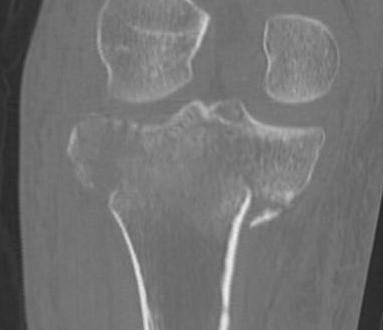

CT scan

Assess joint line

- predetermine fracture pattern before fixation

- will pick up medial condyle / bicondyle / metaphyseal fractures not seen on xray